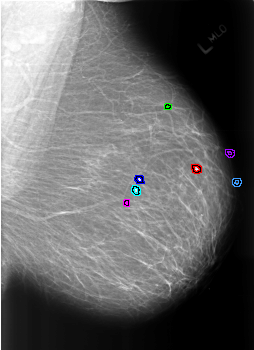

B_3177_1.LEFT_MLO

FILE: B_3177_1.LEFT_MLO.OVERLAY

TOTAL_ABNORMALITIES 7

ABNORMALITY 1

LESION_TYPE CALCIFICATION TYPE EGGSHELL DISTRIBUTION N/A

ASSESSMENT 2

SUBTLETY 5

PATHOLOGY BENIGN_WITHOUT_CALLBACK

ABNORMALITY 2

LESION_TYPE CALCIFICATION TYPE LUCENT_CENTER DISTRIBUTION N/A

ABNORMALITY 3

ABNORMALITY 4

ABNORMALITY 5

ABNORMALITY 6

ABNORMALITY 7